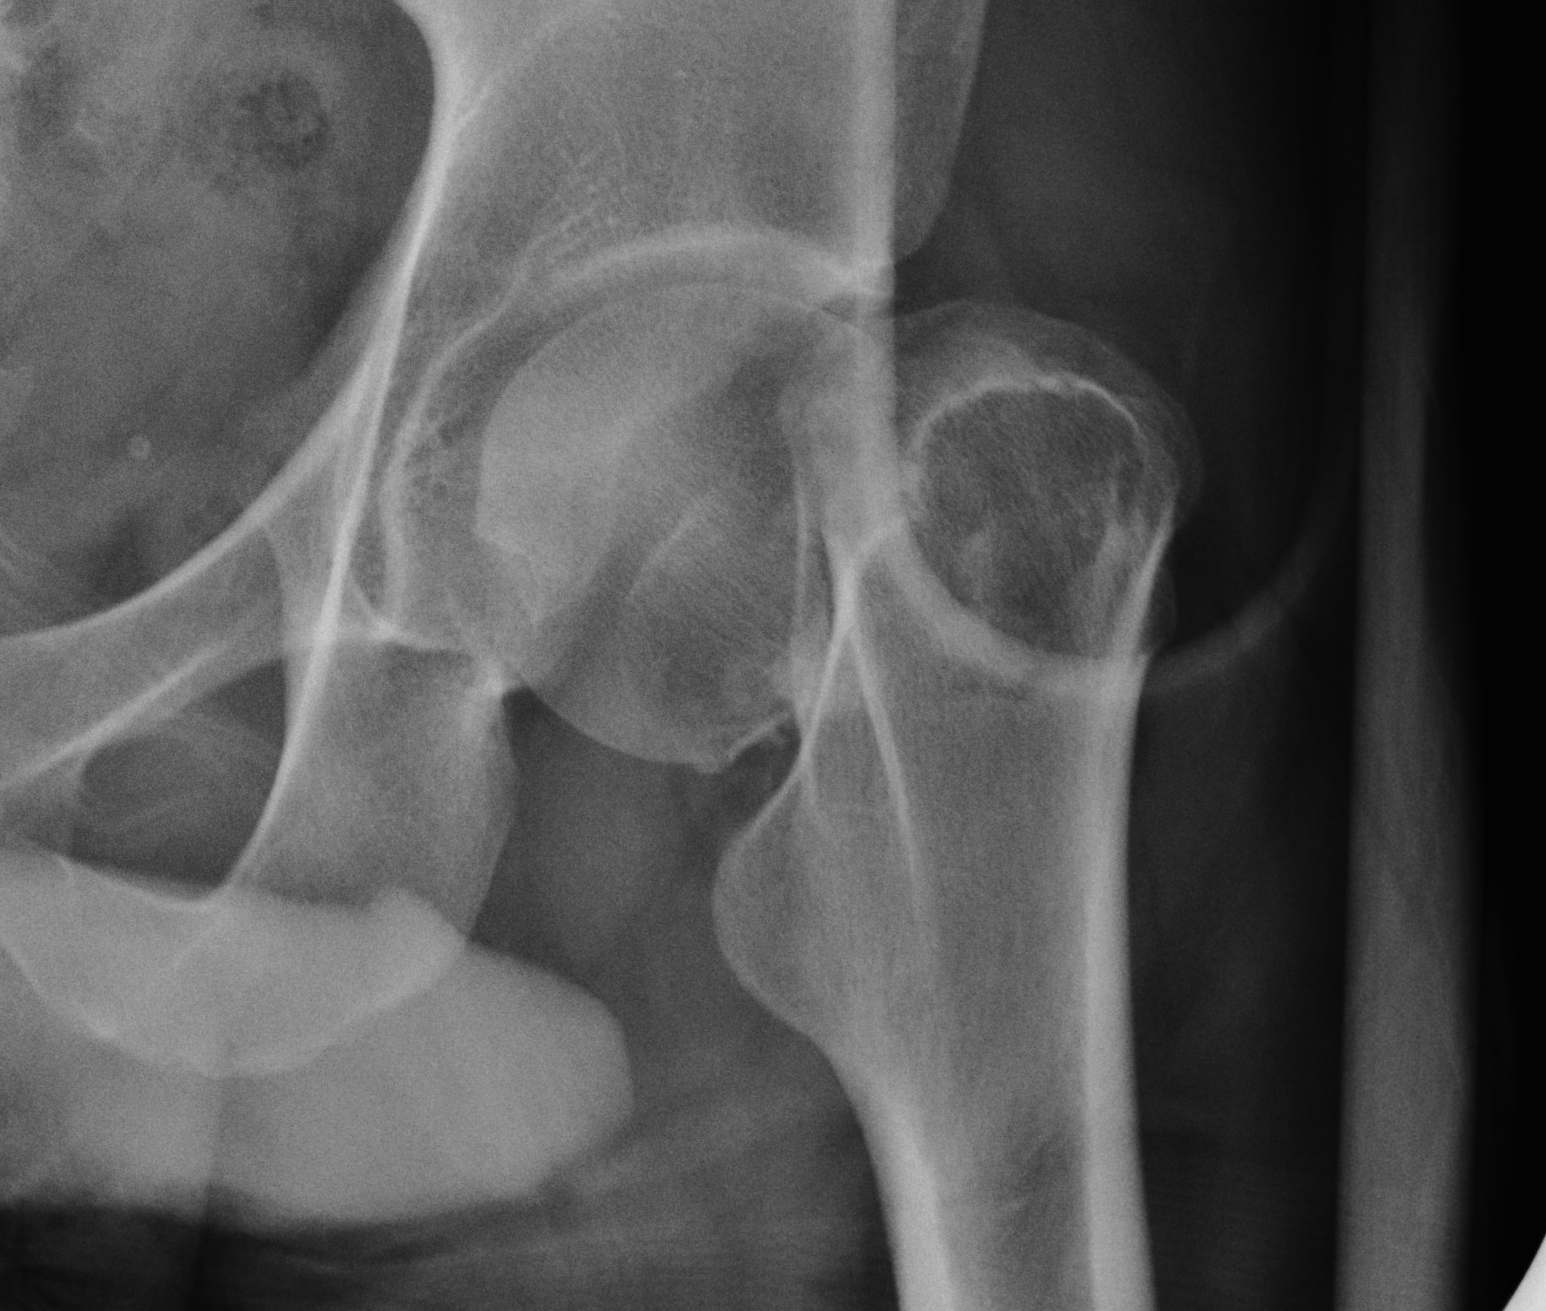

Type III: Complete fracture, partial displaced, trabeculae don't line up with acetabulum

Type IV: Complete fracture, completely displaced, trabeculae line up with acetabulum

Complete fracture Partial displacement Trabeculae don't line up with acetabulum |

Displaced |

| IV |

Complete fracture Complete displacement Trabeculae line up with acetabulum |